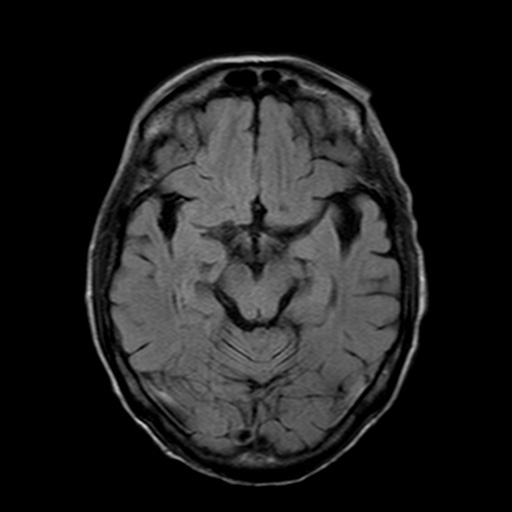

MRIは頭部の断層像で脳腫瘍や梗塞、出血がわかります。MRAは、血管のみ抽出した検査で、くも膜下出血、脳動脈瘤など脳内血管障害の発見に用います。

MRI検査

磁気と電磁波、それに水素原子の動きを利用して、体の断面を撮影する検査で、磁気共鳴画像検査ともいいます。詳細は省きますが、体内の水素が反応して発した信号を捕らえて、コンピューターで解析して画像にしたものです。

MRIではCT検査と同様、腫瘍の大きさや形、数などがわかります。また、MRAでは脳動脈瘤、脳梗塞、脳動静脈奇形、もやもや病、閉塞性動脈病変などの脳血管障害がわかります。脳ドックでは、くも膜下出血の原因となる脳動脈瘤のスクリーニング検査としてよく用いられています。